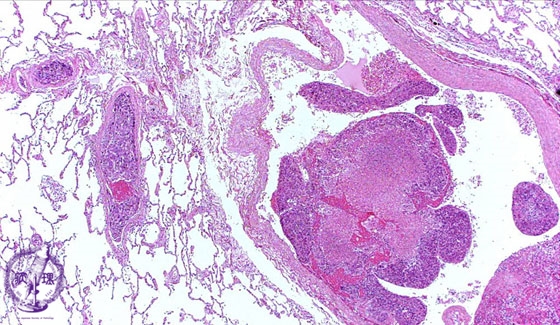

Microscopic view (HE stain, low power view): Large tumor emboli are seen within the pulmonary artery lumen (arrow). There is associated necrosis (dotted line).

Click the image to see the enlarged image.